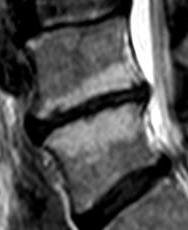

Discopathies L4-L5 et L5-S1 MODIC 1